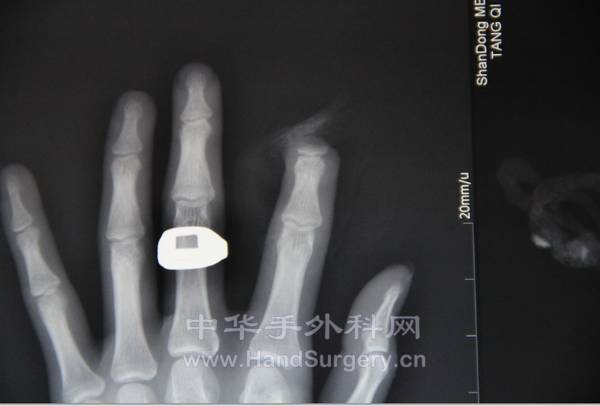

前天值班时候来的一个示指撕脱离断,吵架时被人咬断的,大过年的,有多大的怨恨啊

术前:

X线:

QQ截图20130214163259.png QQ截图20130214163359.png